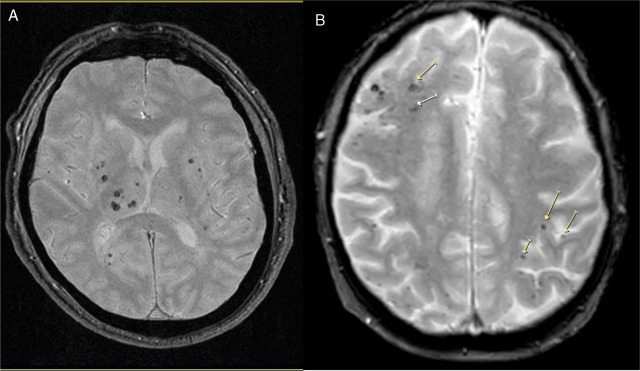

La presencia de enfermedad de vasos cerebrales pequeños en la resonancia magnética de adultos asintomáticos se asoció de manera independiente con un deterioro del funcionamiento ejecutivo durante un período de seguimiento de 8 años en esta población general coreana de edad mediana a avanzada. The Lancet Regional Health Western Pacific, febrero de 2025.

¿Se pueden atribuir los síntomas neuropsiquiátricos a la enfermedad de pequeños vasos cerebrales?

Esta investigación evaluó las consecuencias cognitivas y neuropsiquiátricas de la enfermedad cerebrovascular de vasos pequeños, encontrando que apatía, fatiga y delirio se asociaron con una mayor carga de daño vascular, mientras que las quejas cognitivas subjetivas no lo hicieron. The Lancet Psychiatry, 1º de febrero de 021.